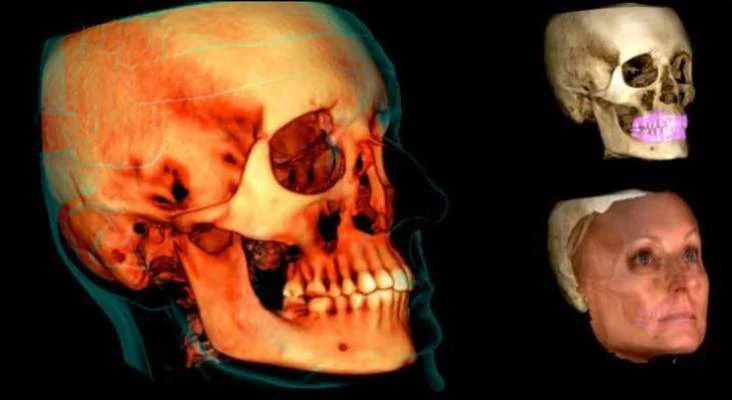

Компьютерная томография (КТ) - революционный метод исследования зубов и челюсти.

Золотым стандартом диагностики в хирургии, имплантологии, ортопедии в настоящий момент является компьютерная томография. Компьютерная томография зубов и челюсти помогает доктору ответить на многие вопросы и составить индивидуальный план лечения пациента.

- Качественные трёхмерные снимки зубов дают возможность планировать весь процесс стоматологической реабилитации с высокой точностью и минимизировать процент возможных осложнений.

3D компьютерная томография челюстей и зубов.

Воссоздавая орган (зуб) или даже совокупность органов, необходимо предельно точно знать исходную ситуацию. Корни зубов, каналы зубов, крупные сосудисто-нервные пучки, идущие внутри костной ткани, верхнечелюстная пазуха во всех подробностях и т.д. - в неискаженном виде все это можно увидеть только на компьютерной томограмме. Стоит ли говорить, что все эти структуры важны для имплантации, так как могут быть легко поврежденфы в ходе операции.